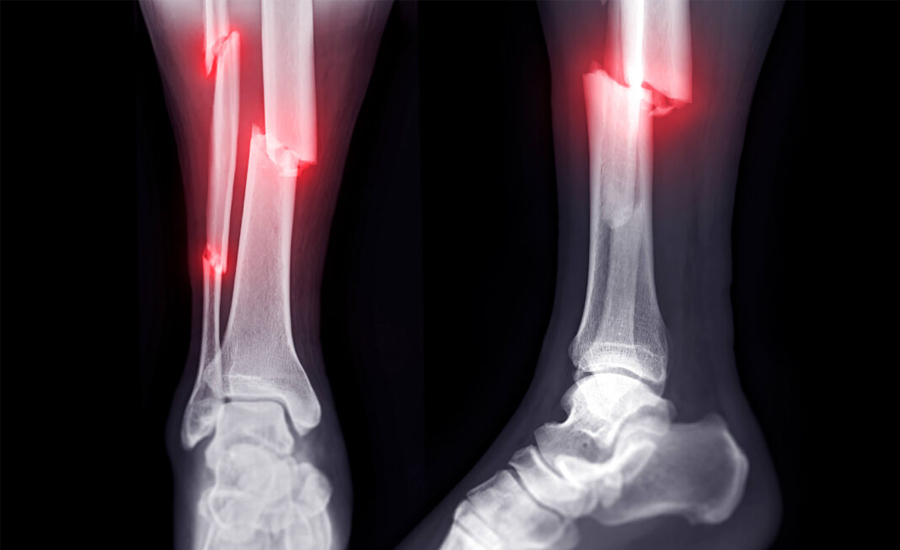

शरीरभित्रका हड्डी विभिन्न कारणले भाँचिन सक्छन् । अक्सर चोटपटक वा दुर्घटनामा पर्दा हड्डी भाँचिने गर्छ । जसलाई ‘ट्रमाटिक फ्याक्चर’ भनिन्छ ।

भाँचिएको हड्डी जोडिने समय बालबालिकामा र वयस्कमा फरक हुन्छ । तर भाँचिएको हड्डी औसतमा ६ हप्तामा जोडिन थाल्छ । ६ हप्तामा दुखाइ कम हुने, भाँचिएको ठाउँ नहल्लिने हुन्छ, त्यसलाई ‘क्लिनिकल युनियन’ भनिन्छ । एक्स-रे हेर्दा त्यसमा हड्डी जोडिएको देखिन्छ भने त्यसलाई ‘रेडियोलोजिकल युनियन’ भनिन्छ ।

सबैको हड्डी ६ हप्तामै जोडिन्छ भन्ने हुँदैन, कसैमा तीन महिना, ६ महिना पनि लाग्न सक्छ, त्यसलाई ‘डिले युनियन’ भनिन्छ । कसैकसैमा भने हड्डी नजोडिने पनि हुन्छ त्यसलाई ‘नन युनियन’ भनिन्छ । हड्डी भाँच्चिंदा घाउ पनि भएको छ भने संक्रमण हुने, ढिलो जोडिने र नजोडिने समेत हुनसक्छ । ६ महिनासम्म पनि हड्डी जोडिएन भने हड्डीलाई जोड्नका लागि ‘बोन ग्राफ्ट’ अन्य ठाउँको हड्डी खुर्केर ल्याएर नजुटेको ठाउँमा भरेर जोडिन्छ ।